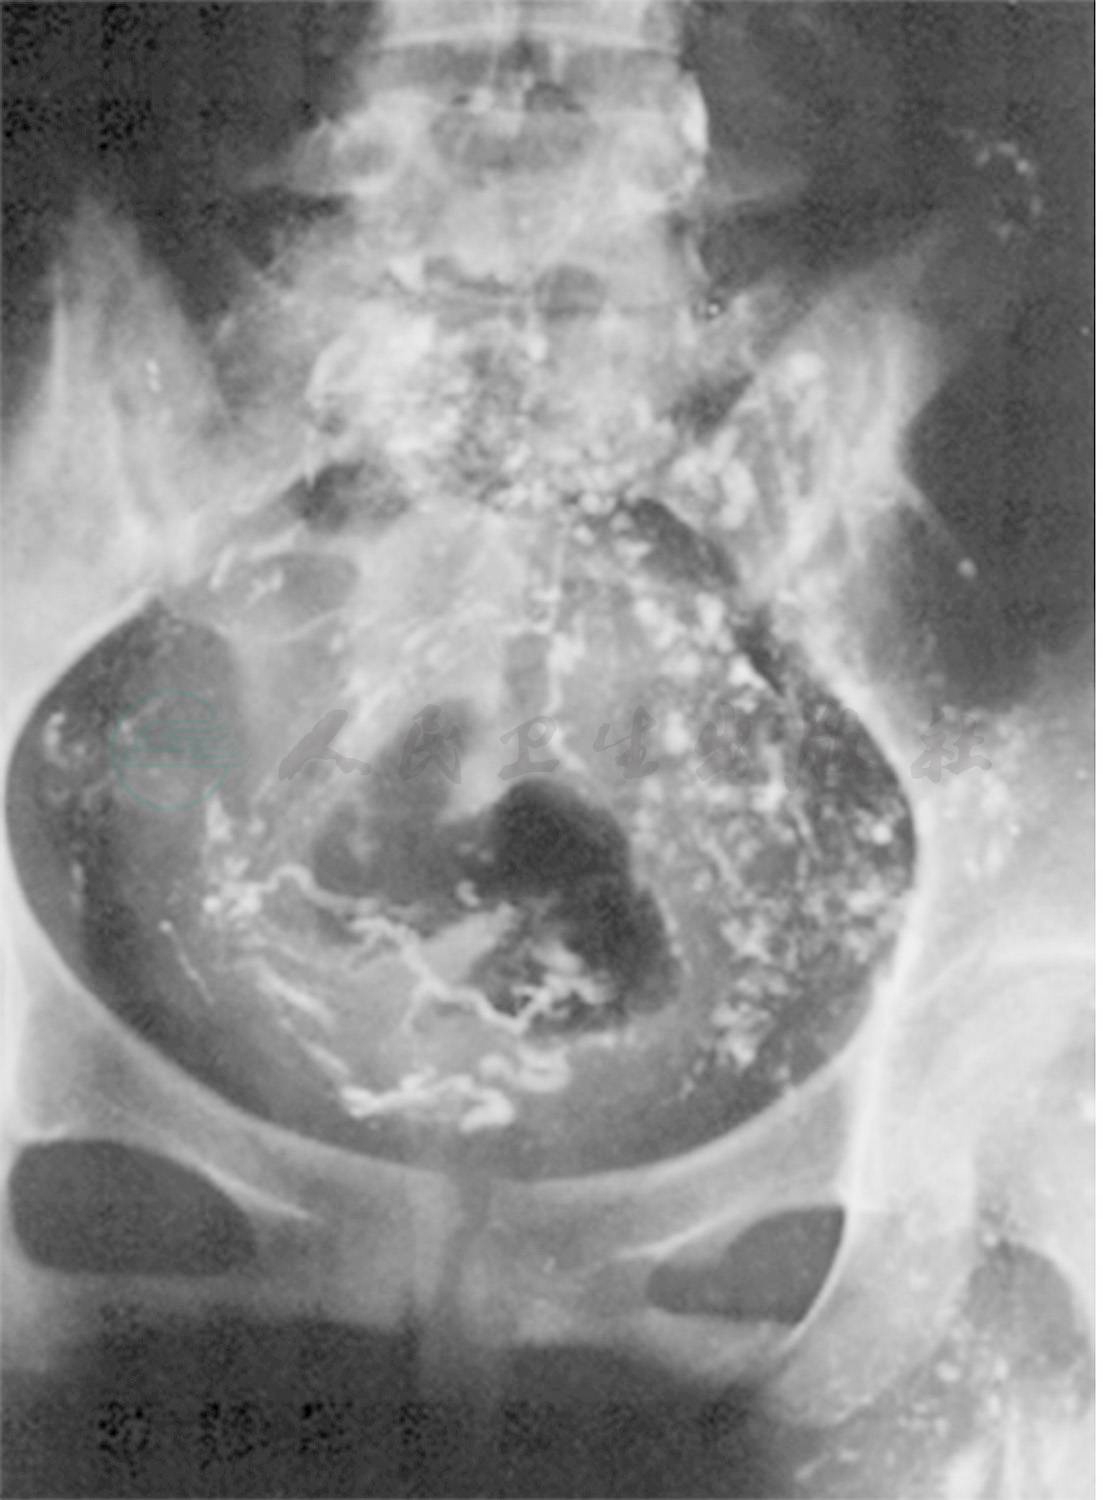

因此,乳糜性腹水可常伴有乳糜性胸水,也可伴有其他部位的乳糜性病变(图4)。

图4女性,58岁,全身核素淋巴显像显示右下肢淋巴水肿,乳糜腹水,左侧乳糜胸